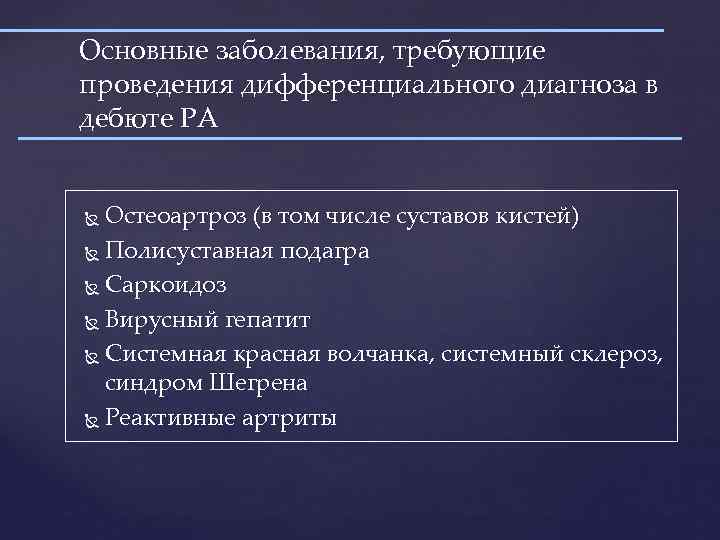

Основные заболевания, требующие проведения дифференциального диагноза в дебюте РА Остеоартроз (в том числе суставов кистей) Полисуставная подагра Саркоидоз Вирусный гепатит Системная красная волчанка, системный склероз, синдром Шегрена Реактивные артриты

Основные заболевания, требующие проведения дифференциального диагноза в дебюте РА Остеоартроз (в том числе суставов кистей) Полисуставная подагра Саркоидоз Вирусный гепатит Системная красная волчанка, системный склероз, синдром Шегрена Реактивные артриты